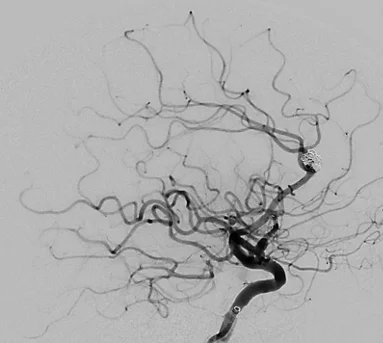

- Angiographie (Darstellung der Gefässe mit Kontrastmittel)

- Abklärung und Beratung bei Gefässfehlbildungen (Aneurysma, arteriovenöse Malformation, arteriovenöse Fistel)